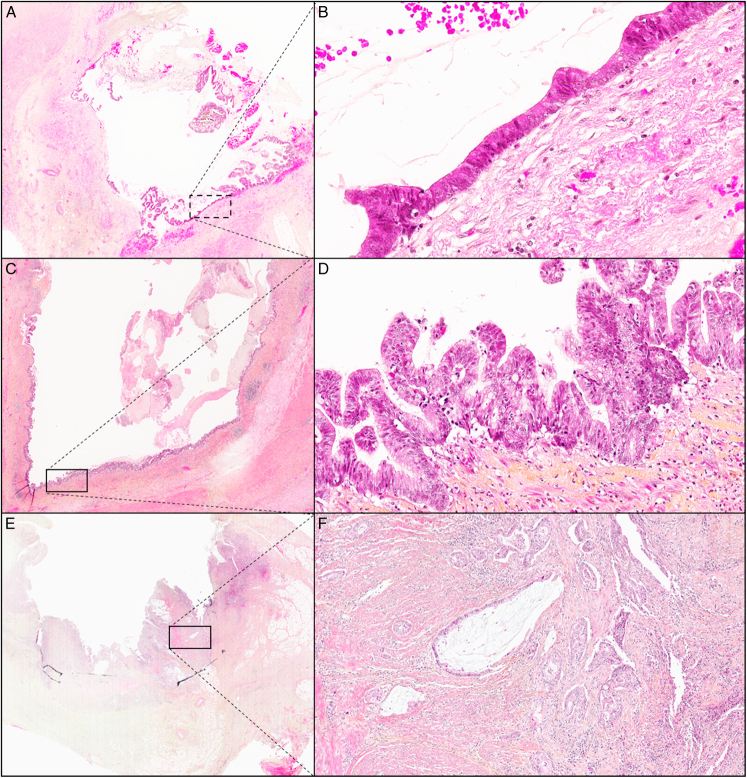

Abstract Image